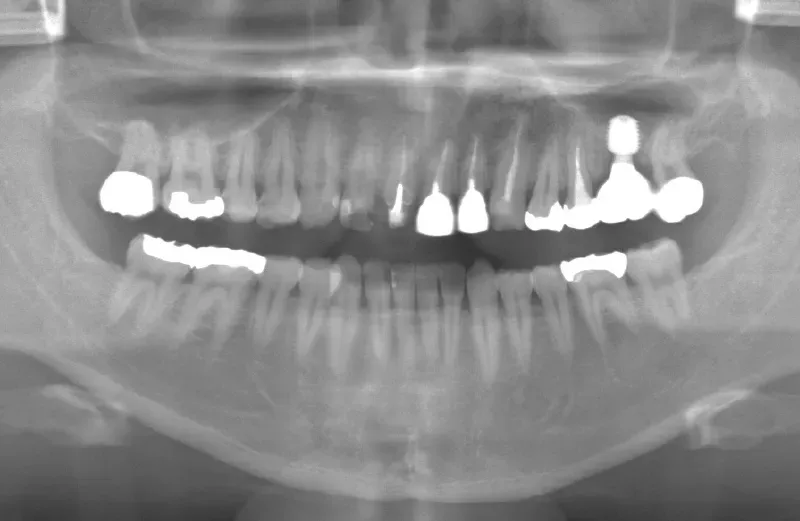

メガジェンオペの症例紹介02

治療前

治療後

| 主訴 | 左上の一番奥歯は他院にてマイクロスコープで治療してもらったが、根の状態が万全ではないのでブリッジでは治療しない方が良いと言われた。 なので左上の歯がないところにインプラントをして欲しい。 |

|---|---|

| 治療期間 | 2ヶ月で仮歯が入り、 3ヶ月で最終補綴物が入って終了。 |

| 費用 | 約550,000円 |

| 治療内容 | エクストラワイドショートインプラントを埋入し、上顎洞を移植材を用いずに挙上しインプラントを埋入した。約2ヶ月で仮歯を装着し、様々な機能面に問題がないことを確認し3ヶ月で最終補綴物を装着して終了した。 |

| 治療のリスク | インプラント埋入オペ時に術者が上顎洞内にインプラントを迷入させる可能性がある。これは術者が技術的に熟練していれば防ぐことが可能。 |